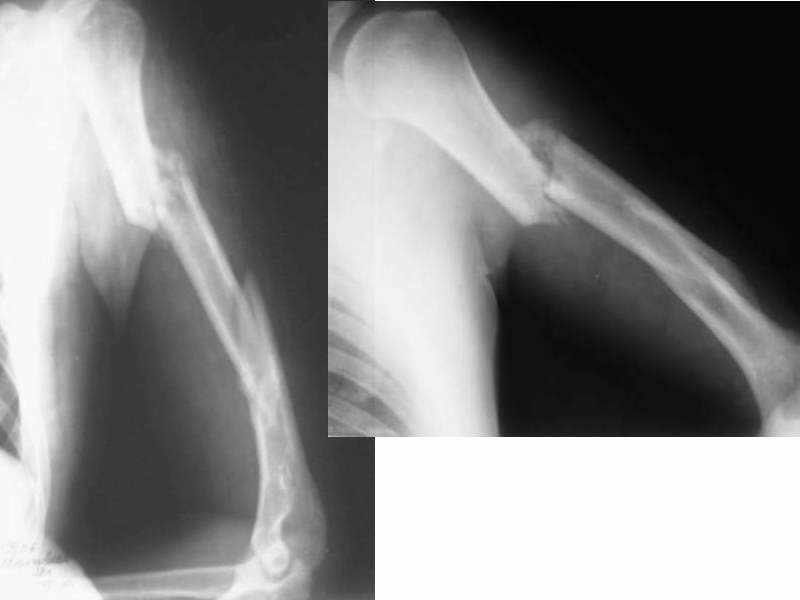

Двойной перелом плеча

Уважаемые коллеги! Больной 28 лет, по профессии монтажник. 30 августа получил изолированную травму: двойной перелом левого плеча(удар бетонной плитой) с парезом лучевого нерва.

Лечился в ЦРБ по месту жительства в травматологическом отделении - гипсовая лонгета по Турнеру. 6 октября попал в НИИТО. Выполнена <ревизия и невролиз лучевого нерва> - цитирую по выписке. Сначала планировался интрамедуллярный остеосинтез, но во время операции выявлена выраженная костная мозоль, остеосинтез не сделали. В настоящее время имеется вот такая картина (см. приложение). Локтевой сустав - контрактура под прямым углом, объем движений в пределах 5 градусов. Плечевой - движения по всем осям - до 45 гр. Лучезапястный - ладонное сгибание - 10 гр., тыльное - 5 гр. Парез лучевого нерва в течение всего времени - без динамики. Выраженный болевой синдром во всех суставах при попытке пассивных движений.

Поступил к нам в сломанной гипсовой лонгете (похоже ее не меняли за все время).Гипс сняли. Клинически - подвижности в зоне переломов и болей нет.

Какая тактика предпочтительна - оставить все как есть и заниматься устранением конрактур, или все-таки попытаться исправить ось плеча, заштифтовать и затем начать функциональное лечение?